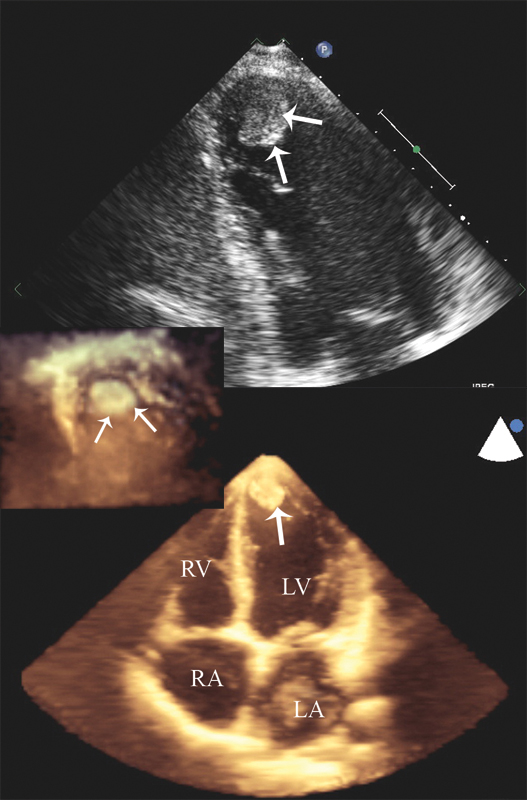

فحوصات تشخيصية لبعض امراض القلب والشرايين التاجية